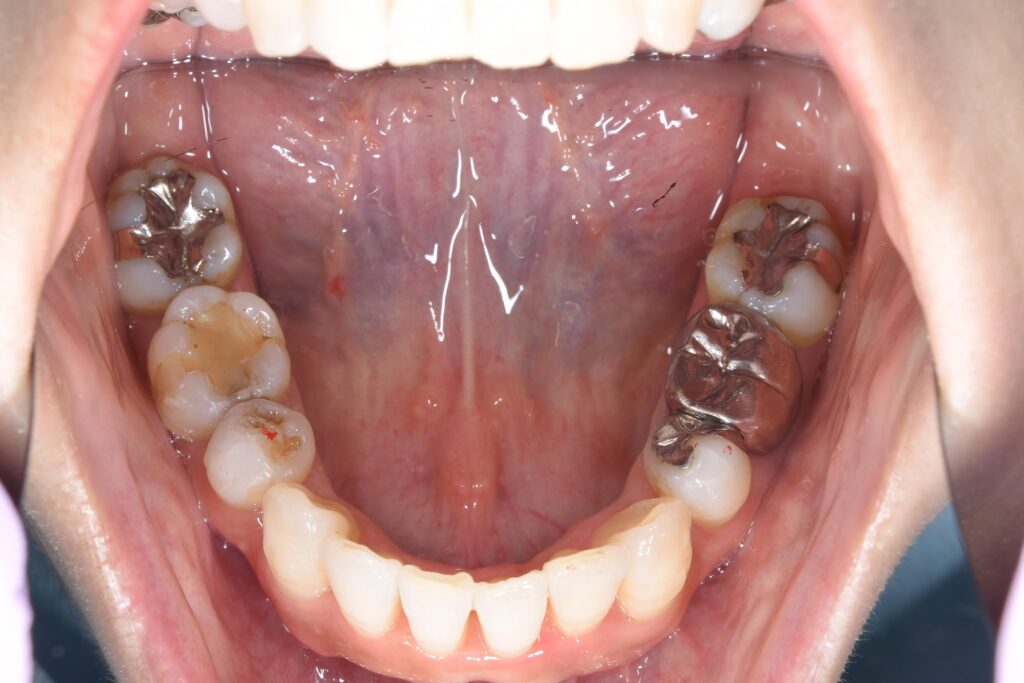

以下に術後8カ月の状態です。(まだ、微調整が必要なため終了ではありません)

【矯正開始8カ月後】

いかがでしょうか。

マウスピースを適切に使用して頂けたおかげで、ここまで改善することができました(^^♪

この患者様は合計4本の抜歯を行いこの状態になりました。